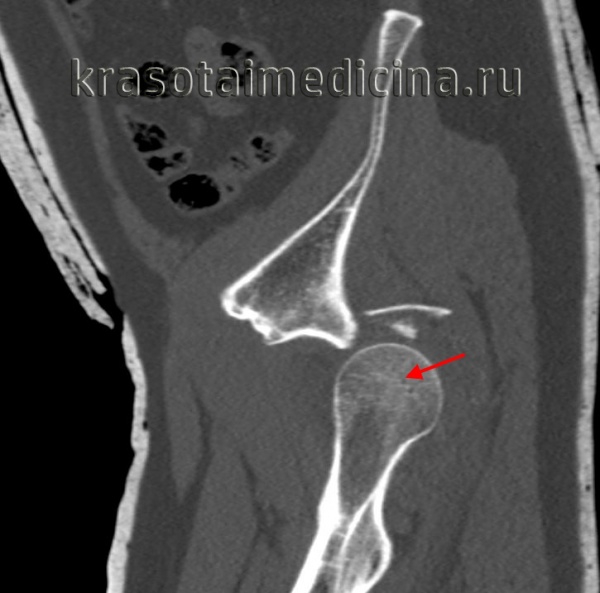

Rg правого тазобедренного сустава. Врожденный вывих бедра. Головка бедренной кости (красная стрелка) ремоделирована, уплощена, смещена краниально. Вертлужная впадина (синяя стрелка) недоразвита.